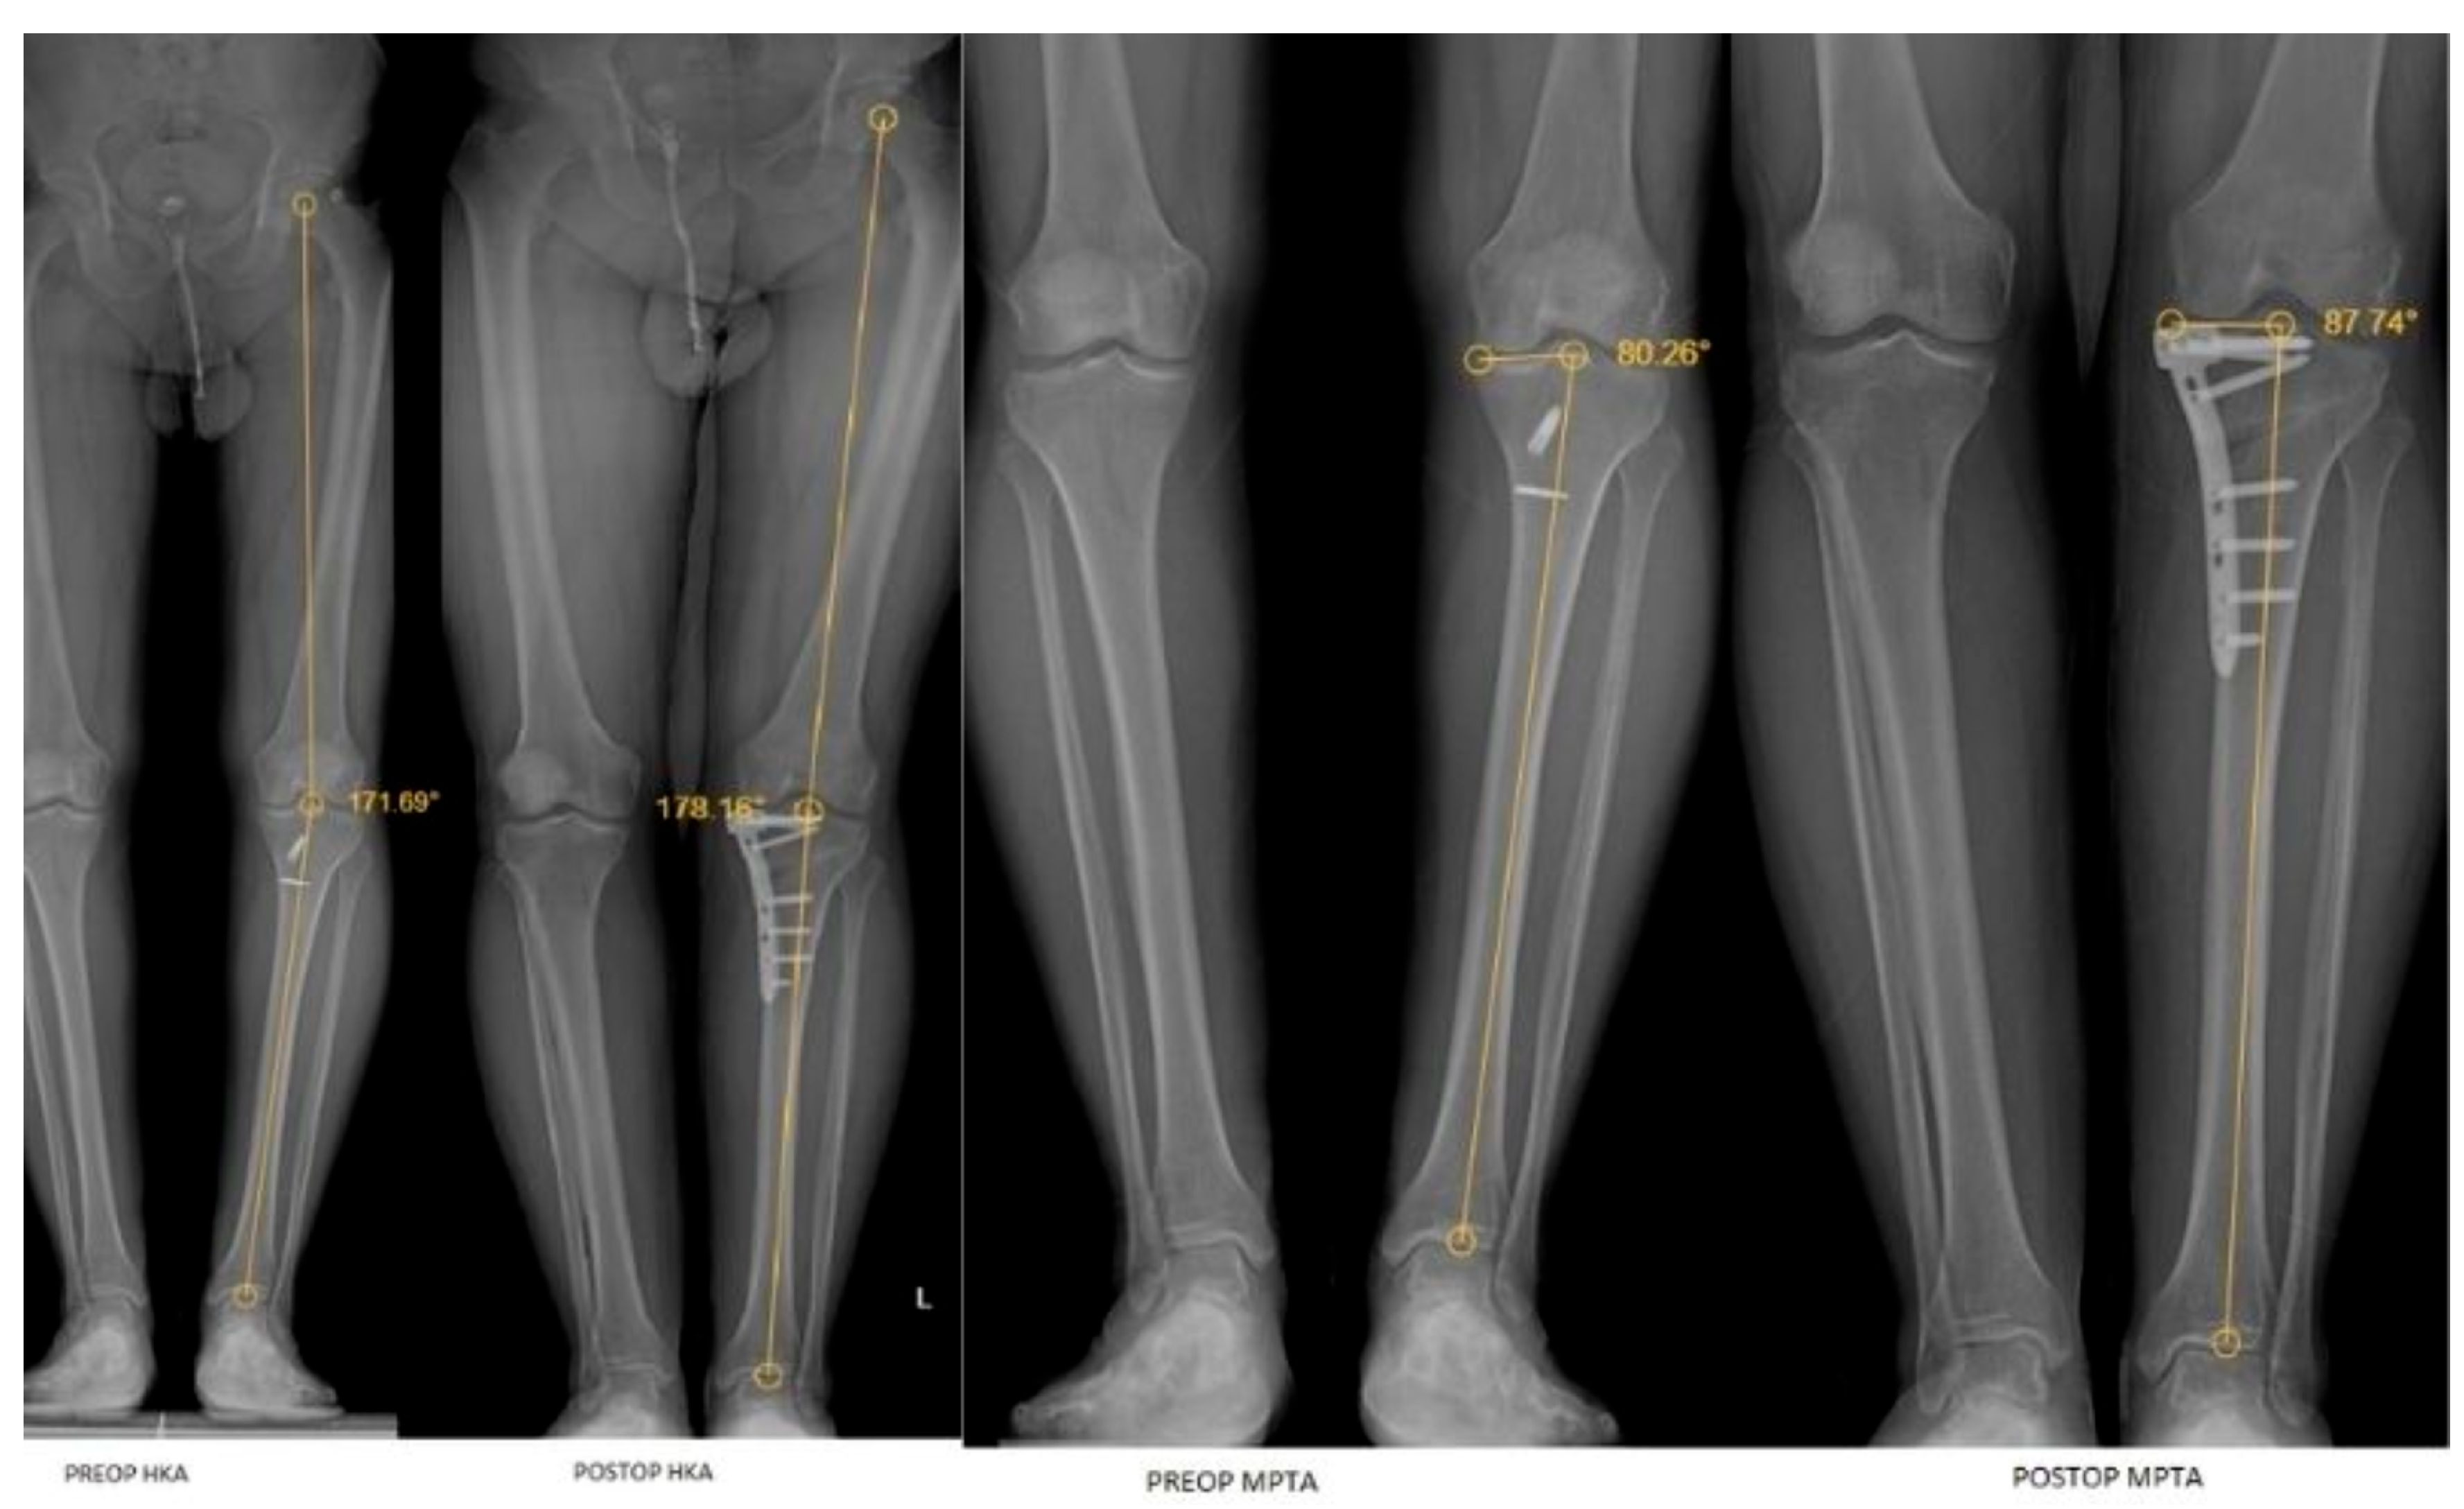

| LDTA | 87.25 (2.76) | 88.14 (2.24) | 0.018 a | 0.225 | 0.690 (0.577–0.776) |

| MPTA | 83 (4.53) | 87.40 (2.71) | <0.001 a | 0.838 | 0.441 (0.277–0.579) |

| HKA | 171.44 ± 3.35 | 177.11 ± 2.32 | <0.001 b | −1.804 | 0.404 (0.235–0.549) |

| JLCA | 3.18 (1.94) | 1.95 (1.12) | <0.001 a | 0.798 | 0.692 (0.580–0.778) |